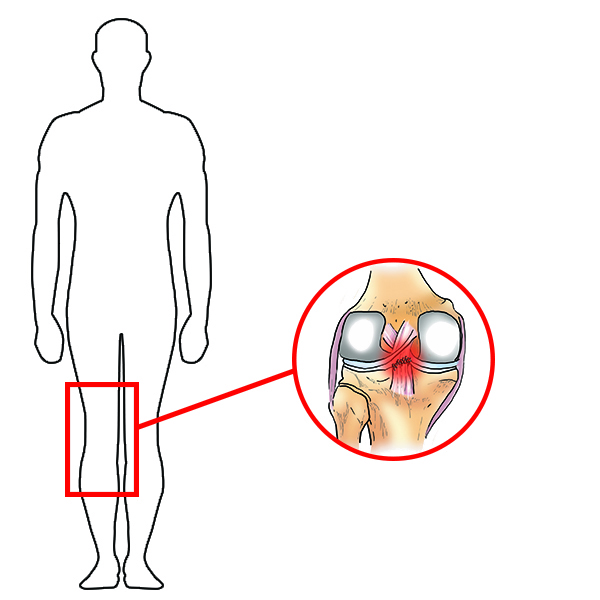

USZKODZENIE WIĘZADŁA KRZYŻOWEGO TYLNEGO (PCL)

Więzadło krzyżowe tylne (PCL) to solidne pasmo tkankowe, łączące kość udową z piszczelą, które jest znacznie mocniejsze niż ACL. Wraz z więzadłem krzyżowym przednim (ACL) zabezpieczają dolną część kości udowej i górną część kości piszczelowej, co pozwala na utrzymanie tych dwóch kości wspólnie i formowanie stawu kolanowego. Więzadła krzyżowe stawu kolanowego pozwalają nam żyć aktywnie: skakać, pływać czy biegać. Problem polega na tym, że podczas tych aktywności więzadła krzyżowe oraz okoliczne tkanki miękkie mogą zostać łatwo uszkodzone. Wraz z uszkodzeniem PCL bardzo często dochodzi do zerwania innych więzadeł kolana, a także do uszkodzenia chrząstki stawowej czy łąkotki.

Więzadła krzyżowe stawu kolanowego pozwalają nam żyć aktywnie: skakać, pływać czy biegać. Problem polega na tym, że podczas tych aktywności więzadła krzyżowe oraz okoliczne tkanki miękkie mogą zostać łatwo uszkodzone. Wraz z uszkodzeniem PCL bardzo często dochodzi do zerwania innych więzadeł kolana, a także do uszkodzenia chrząstki stawowej czy łąkotki.

Ponadto, do urazu więzadła krzyżowego tylnego (PCL) bardzo często dochodzi podczas uprawiania sportów. Dyscypliny, w których najczęściej dochodzi do tego typu urazu to gry, w których następuje gwałtowna zmiana ruchów: od szybkiego przemieszczania się, po skręty, podskoki i wymienne przenoszenie środka ciężkości na kończyny. Do sportów, w których PCL jest narażony na uszkodzenie zaliczamy: piłkę nożną, koszykówkę, narciarstwo, sporty walki oraz sporty motorowe.